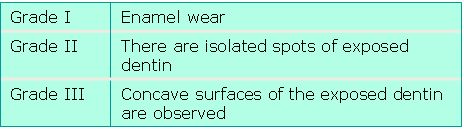

25 temporary teeth were obtained from 20 patients who came to the Pediatric Dentistry Department of the School of Dentistry, Universidad Nacional del Nordeste located in the capital of Corrientes, Argentina, for dental care. The patients considered were children aged between 4 and 12, of both sexes, whose clinical records were prepared, including their family history and diet chart, and the odontogram was filled in. The tooth was photographed before extraction and the written informed consent of a parent or guardian was requested. The sample was processed and identified with the following information: patient identification, date, material obtained, method used to obtain it, clinical data. Samples were fixed using physiological saline solution in order to prevent dessication and loss of properties. The following details were recorded before processing the samples: tooth organ, affected surface of the tooth and extent of attrition measured in millimeters. Most of the teeth obtained were from the anterior sets of teeth, which was deemed normal, taking into account that the age of the patients that come for dental care to the Pediatric Dentistry Department ranges between 4 and 7 years of age. This is consistent with the exfoliation period of these organs, unlike the other groups of teeth. The degree of attrition of each tooth and group of teeth was determined, with attrition being defined as the physiological tooth wear resulting from the contact between teeth during mastication. The teeth were classified according to a modified Gerasimov’s tooth wear scale, as agreed by the work group, in which degrees 1, 5 and 6 of the original scale were not taken into account because they were deemed to be irrelevant for this research, since grade 1 is for absence of wear, grade 5 for a fully exposed crown and 6 for absence of dental crown (completely worn off). Due to the above, the Gerasimov scale used in this study was modified taking into account the observed tooth wear, and ranges between grade I and III, as shown in Fig. 2.

Fig. 2. Modified Gerasimov’s tooth wear scale

25 temporary teeth were obtained from 20 patients who came to the Pediatric Dentistry Department of the School of Dentistry, Universidad Nacional del Nordeste located in the capital of Corrientes, Argentina, for dental care. The patients considered were children aged between 4 and 12, of both sexes, whose clinical records were prepared, including their family history and diet chart, and the odontogram was filled in. The tooth was photographed before extraction and the written informed consent of a parent or guardian was requested. The sample was processed and identified with the following information: patient identification, date, material obtained, method used to obtain it, clinical data. Samples were fixed using physiological saline solution in order to prevent dessication and loss of properties. The following details were recorded before processing the samples: tooth organ, affected surface of the tooth and extent of attrition measured in millimeters. Most of the teeth obtained were from the anterior sets of teeth, which was deemed normal, taking into account that the age of the patients that come for dental care to the Pediatric Dentistry Department ranges between 4 and 7 years of age. This is consistent with the exfoliation period of these organs, unlike the other groups of teeth. The degree of attrition of each tooth and group of teeth was determined, with attrition being defined as the physiological tooth wear resulting from the contact between teeth during mastication. The teeth were classified according to a modified Gerasimov’s tooth wear scale, as agreed by the work group, in which degrees 1, 5 and 6 of the original scale were not taken into account because they were deemed to be irrelevant for this research, since grade 1 is for absence of wear, grade 5 for a fully exposed crown and 6 for absence of dental crown (completely worn off). Due to the above, the Gerasimov scale used in this study was modified taking into account the observed tooth wear, and ranges between grade I and III, as shown in Fig. 2.

Fig. 2. Modified Gerasimov’s tooth wear scale